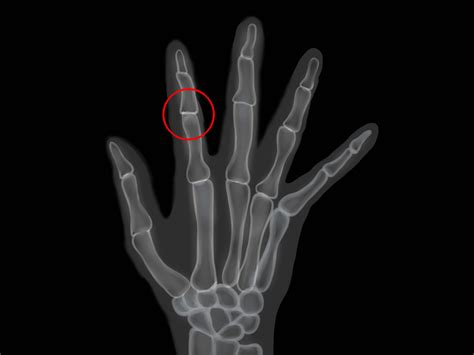

Rheumatoid Arthritis Therapies

Rheumatoid Arthritis Therapies